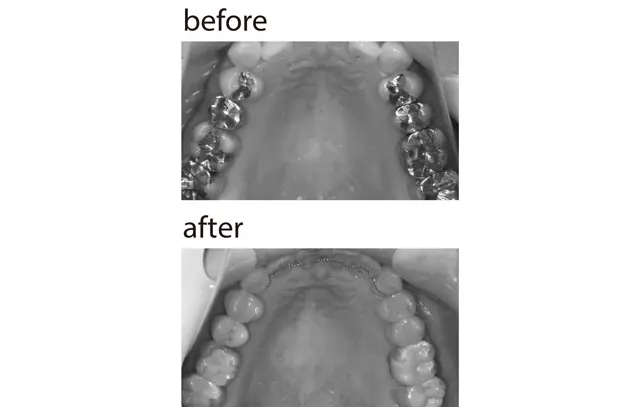

奥歯4本ずつの銀歯をセラミックに変え、前歯には裏側ワイヤー矯正も。人に見せたくなる仕上がりに